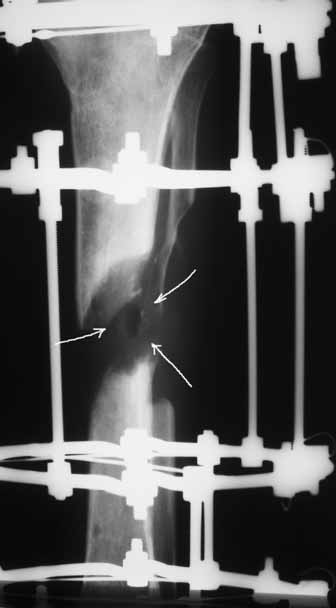

Ввиду относительной тугоподвижности ложного сустава и наличия признаков репаративной активности костной ткани рентгенологически, после 10 дней компрессии на стыке отломков, начали дистракцию по 1мм в день. Выписан на амбулаторное лечение. Отделяемое в нижней трети голени прекратилось, ранка закрылась. Интраоперационно и 5 дней после операции получал ципроксациллин. В июле по передней поверхности голени в зоне регенерата открылась ранка с обильным гнойным отделяемым. После локального лечения, ранка в течении двух недель эпителизировалась и полностью закрылась. Дистракцию не прекращали. (during 1, 2)

10 дней назад ранка на передней поверхности средней трети голени и по внутренней поверхности нижней трети голени, (по проекции стержня апп.Гофмана) открылись вновь. В настоящий момент отделяемого из обеих ран нет (wound1;2).

Рентгенологически определяется дистракционный регенерат удовлетворительной плотности и наличие в нем полости (now 1;2;3).